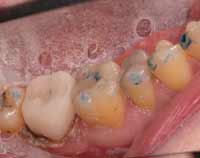

Case 1: Scientific Articulation

The following case illustrates the concerns about using articulating paper alone for occlusion. The patient had an all-ceramic restoration placed to fix a previously fractured tooth. This case initially was completed before using an objective scanning device for occlusion analysis. The all-ceramic crown failed shortly after placement. Figure 1 shows the subsequent replacement crown immediately after milling and before characterization, glazing, and final insertion. Checking the occlusion with 20-μm articulating paper produced what appeared to be very light contact on tooth No. 31. Figure 2 shows the subsequent T-Scan III analysis of the same patient.

The computerized analysis showed that even with very light articulating paper markings there were excessive forces being placed on the area around tooth No. 31. The 3D graph showed the exact area that needed to be adjusted for this discrepancy. Because this area of concern was previously undetectable with articulating paper alone, it may be the cause of the initial failure of the patient’s tooth. The new all-ceramic crown placed after using T-Scan III analysis and adjusting the occlusion based on the finding solved this problem. Whereas the original restoration fractured within 1 month, the subsequent replacement, as of this writing, has lasted for more than 2 years without failure.

Figure 1 The replacement crown immediately after milling and use of articulating paper. Note that this method produced what appears to be very light contact on tooth No. 31.